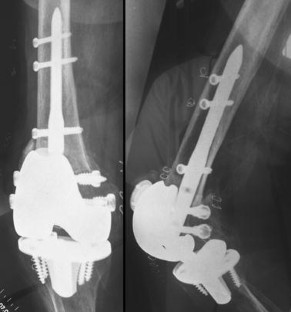

Abb. 1